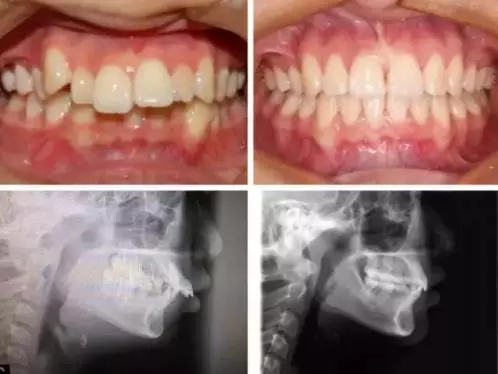

当然,每个个体的生理情况不一样,牙齿的移动速度不同,矫正时间也会不同,另外有一种情况必要要了解,骨性的矫正,尤其是骨性龅牙,因为牙槽骨非常致密,改建过程较困难,所以矫正时间相对要增加,通常会超过2年甚至更长。